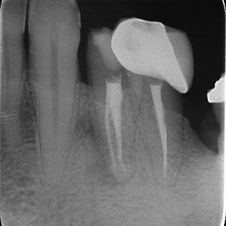

טיפול שורש בשן עם מורפולוגיה חריגה

במקרים בהם לשן יש צורה חריגה, נדרש שימוש בציוד ומכשור מיוחדים, וזאת לאחר תכנון הטיפול בעזרת צילומים תלת-ממדיים (CBCT) שנותנים מידע מדויק על האנטומיה של השן .